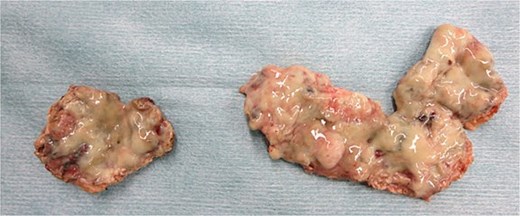

Emergency laparoscopic surgery was initiated for diffuse peritonitis. Although copious purulent ascites was observed, no gastrointestinal perforation was identified. Instead, two perforations with purulent discharge were found in the enlarged uterine body, confirming ruptured pyometra (Fig. 2a). Given the patient’s advanced age, comorbidities, and hemodynamic instability, hysterectomy was considered excessively invasive. The uterine wall was therefore incised, and purulent material was drained (Fig. 2b). Partial resection of the uterine wall was performed to maintain an open abscess cavity and facilitate continuous drainage (Fig. 2c). The abdominal cavity was irrigated with 8 L of warm saline, and drains were placed in the bilateral subdiaphragmatic spaces, uterine cavity, and Douglas pouch. Operative time was 2 h 4 min with minimal blood loss. Histopathology showed inflammatory cell infiltration with edema and necrosis, without evidence of malignancy (Fig. 3).

Resected uterine wall: An abscess adherent to the inner surface of the resected uterine wall.